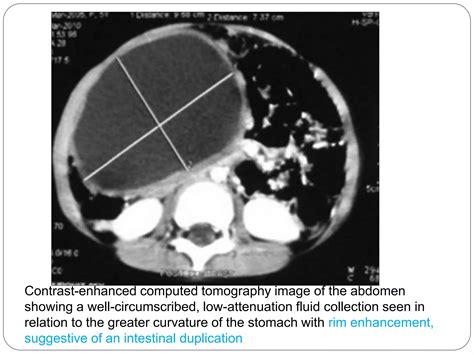

Because the symptoms of a cyst in stomach are often non-specific and mimic other digestive disorders like gastritis or ulcers, doctors rely on imaging technology to pinpoint the location and nature of the growth. Diagnosis typically follows a structured approach to differentiate between benign cysts and more serious conditions.

CT Scan Provides detailed cross-sectional images of the abdominal organs.